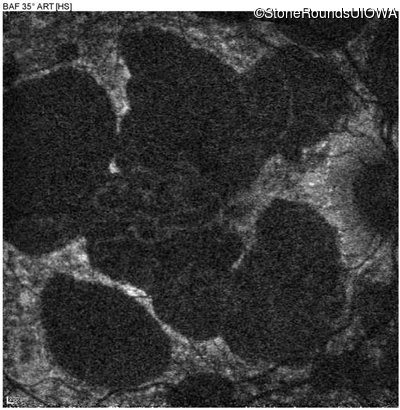

Blue Autofluorescence - Right - 20/40 -2

Exemplar

Blue Autofluorescence - Left - 20/40 +1